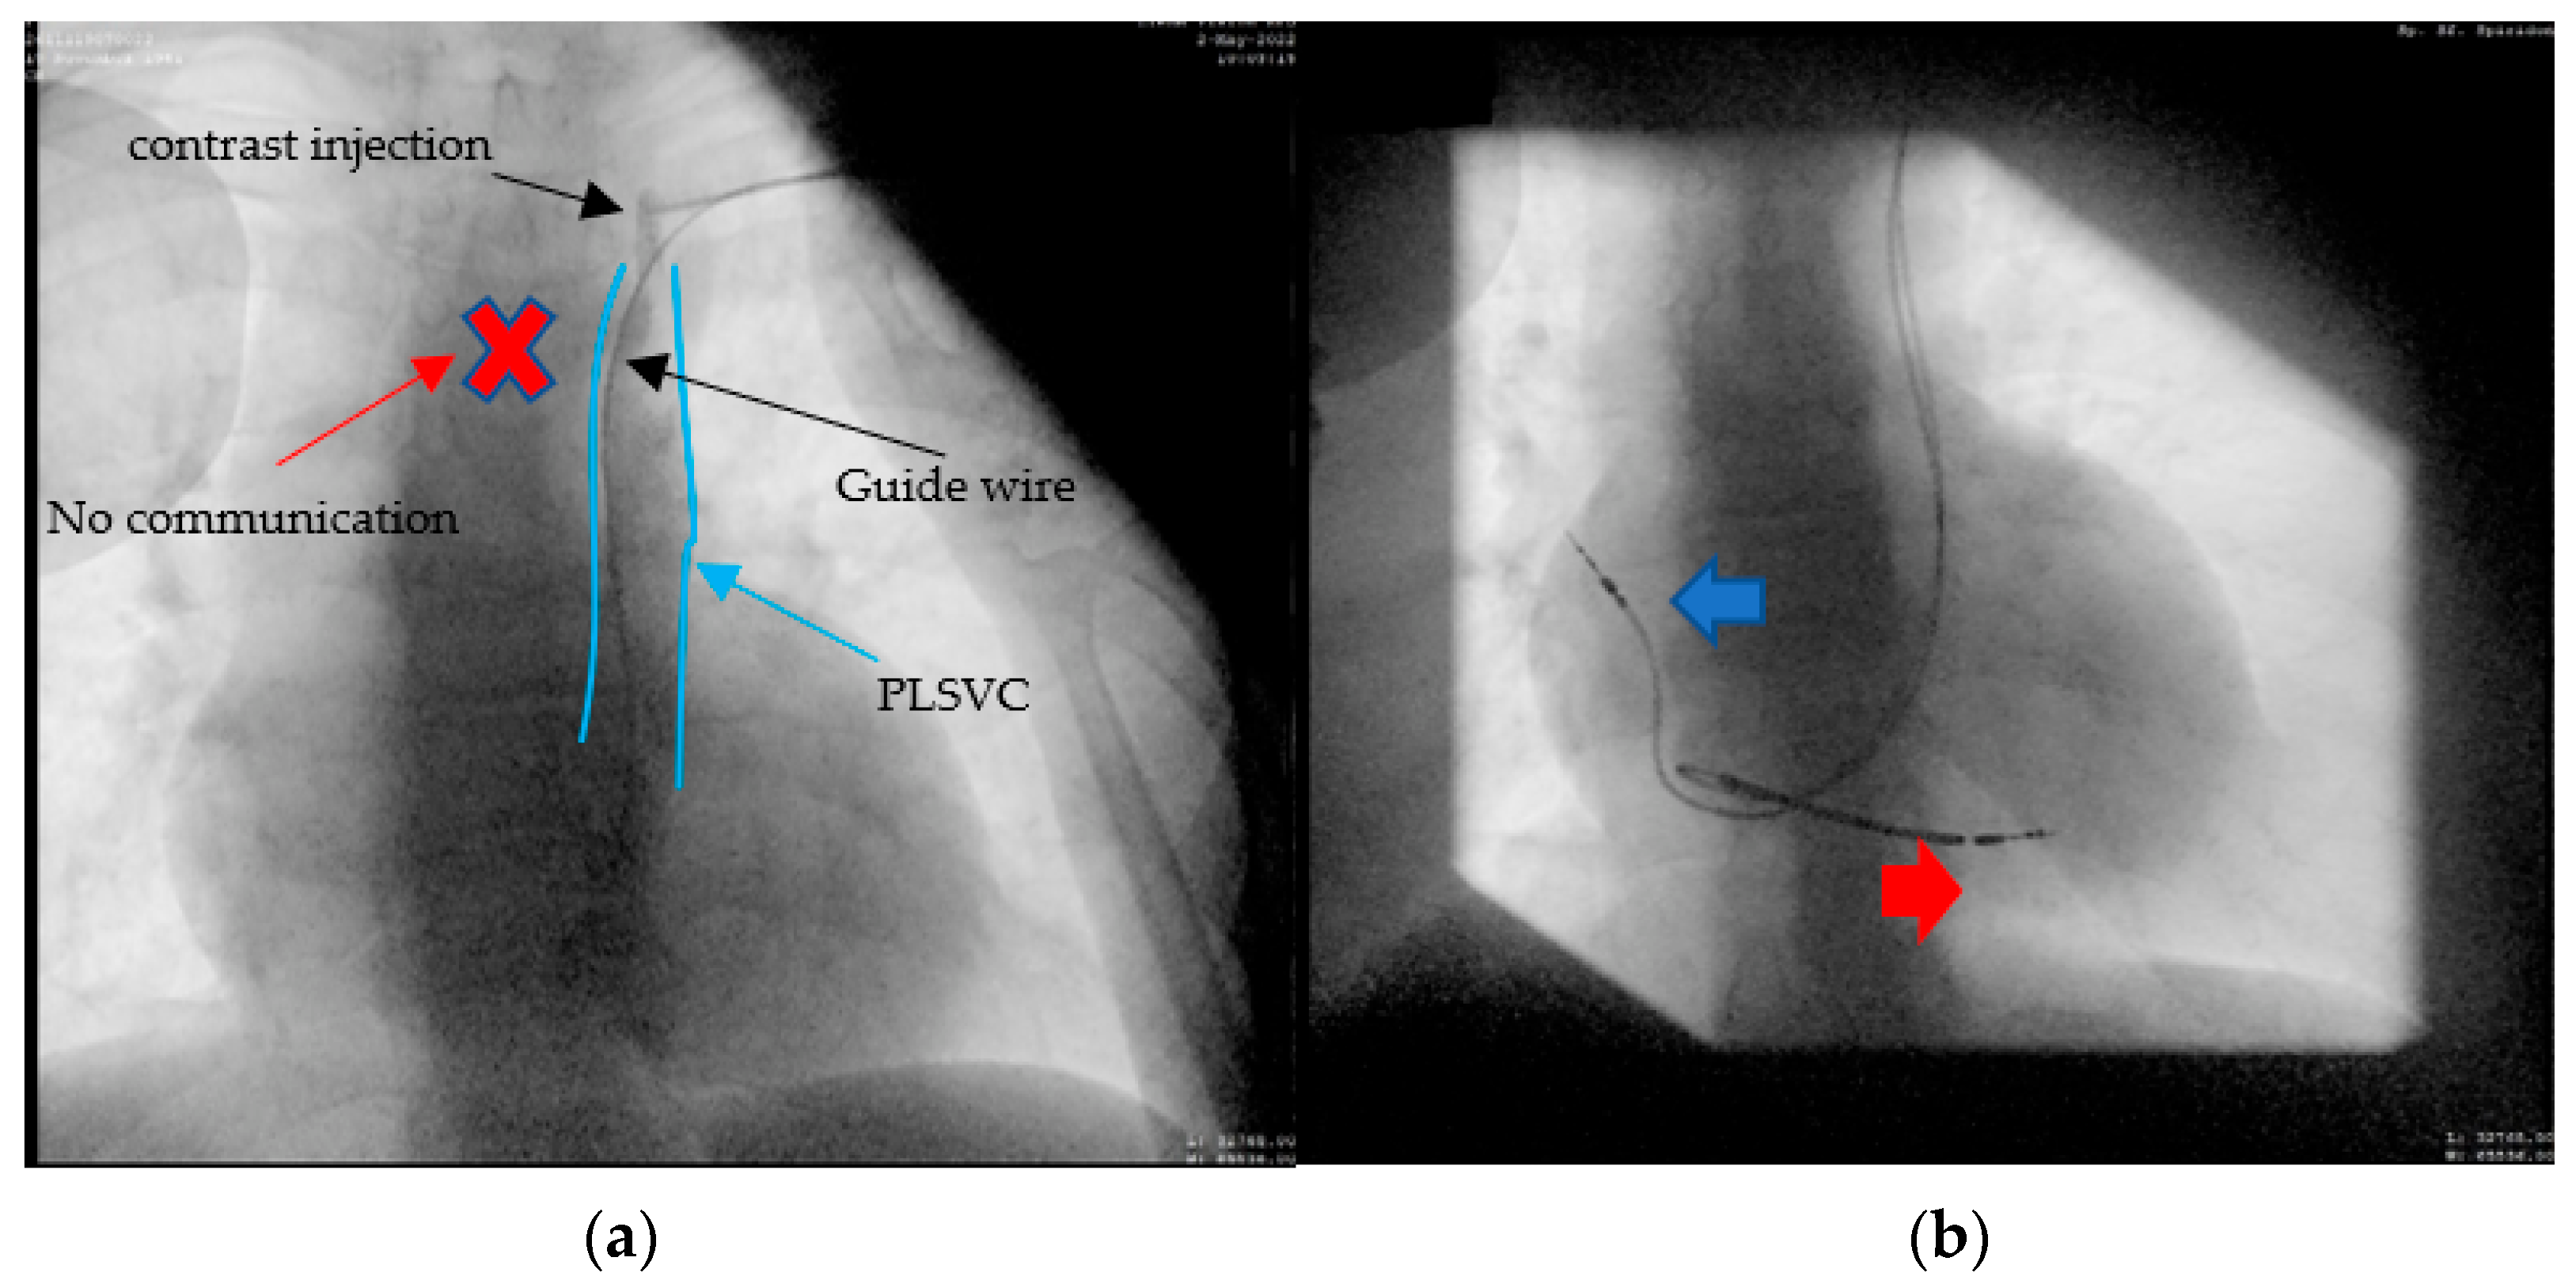

A 60-year-old female patient, with multiple cardiovascular risk factors (diabetes, dyslipidemia, hypertension), diagnosed with dilated cardiomyopathy with an ejection fraction of 15% and LV diameter of 64 mm 6 months ago, under maximal treatment for heart failure, was referred to our center after being diagnosed with sick sinus syndrome (tachycardia–bradycardia syndrome: sinus bradycardia alternating with paroxysmal atrial flutter) based on 24 h Holter ECG monitoring, symptomatic through syncope. A coronary angiography was performed, revealing normal epicardial coronary arteries, thus excluding an ischemic cause for the dilated cardiomyopathy. According to the current guidelines [9] in the primary prevention of sudden cardiac death, the next step was the implantation of a bicameral implantable cardioverter defibrillator (ICD). Left subclavian access was performed, but fluoroscopic evaluation again revealed an abnormal trajectory of the guide wire, raising the suspicion of a venous anomaly. Same as in case 2, the venography was performed through the subclavian vein, which evoked a persistent left superior vena cava, without any communication with the right superior vena cava (Figure 6a). Post-procedurally thoracoabdominal angio-CT revealed the presence of the right superior vena cava (type IIIb). This time, a 9F defibrillation lead (Medtronic Spring Quattro™, length 62 cm) was advanced through the coronary sinus in the right atrium, and again, using a J-shaped stylet, to the right ventricle, where it was placed at the apical level. In this case, we encountered some difficulties as we advanced the lead, which we passed by slightly retracting the stylet and leaving the tip of the probe free. After that, we placed the atrial lead at the right atrium level (Figure 6b).

Figure 6.

(a) The passage of the guide wire to the left side of the spine and then the venography confirming the presence of PLSVC, no communication with the right vena cava can be seen; (b) the defibrillation leads can be seen on the trajectory of the left superior vena cava (LSVC), through the coronary sinus (CS) into the right ventricular apex (RV)—red arrow. The atrial lead can be seen through the LSVC, coronary sinus, and right ventricle in the right atrial appendage (RA)—blue arrow.